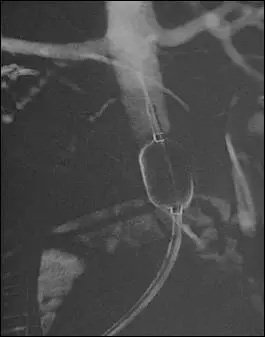

山东省立医院产科于2013年10月采取腹主动脉球囊阻断下辅助凶险性前置胎盘剖宫产术。球囊于剖宫产前经股动脉插管在腹主动脉下段预置球囊,选择尽量避开胎盘的子宫切口切开子宫娩出胎儿后立即充盈球囊阻断腹主动脉,药物促进宫缩,结扎子宫动脉上行支、徒手剥离胎盘并尽量清除植入肌层的胎盘组织,分离反折腹膜、下推膀胱,采用可吸收线局部缝扎、折叠缝合、CHO四边形缝合和B-Lynch缝合以控制产后出血。腹主动脉球囊阻断后,多数效果良好,出血减少,子宫切除率明显下降,由79.3%降至18%,超过80%的凶险性前置胎盘患者保住了子宫。这得利于胎儿娩出后充盈的球囊阻断了腹主动脉,出血明显减少,术野清晰,利于手术操作和精准止血,为保留子宫创造了条件。目前我院产科与影像研究所介入科合作已经完成腹主动脉球囊阻断下辅助凶险性前置胎盘剖宫产250余例,效果良好,国内处于领先地位。术中出血量和输血量明显减少,周围脏器损伤减少,患者转至ICU病房治疗天数减少。保留子宫的手术操作并没有增加术后感染和介入手术操作的严重并发症。关于胎儿的安全性,由于在腹主动脉下段预置球囊的辐射剂量约12-25mGy,明显小于对胎儿的损害剂量,对胎儿安全。

在经过一段时间保胎治疗后,9月23日,产科请麻醉科、泌尿外科、介入科、妇科等专家行疑难病例讨论,并于9月26日在介入科行腹主动脉下段放置球囊,然后到手术室在全麻下行子宫体剖宫产术+前置胎盘B-Lynche缝合术+B-Lynche缝合术。手术顺利,麻醉满意,术中失血2500ml,输红细胞6u,血浆200ml,补液3500ml,术后患者各项生命体征平稳,直接转入外科ICU。新生儿转儿科治疗。患者于术后第2天转入产科,给予抗炎补液支持治疗,腹部刀口甲级愈合。